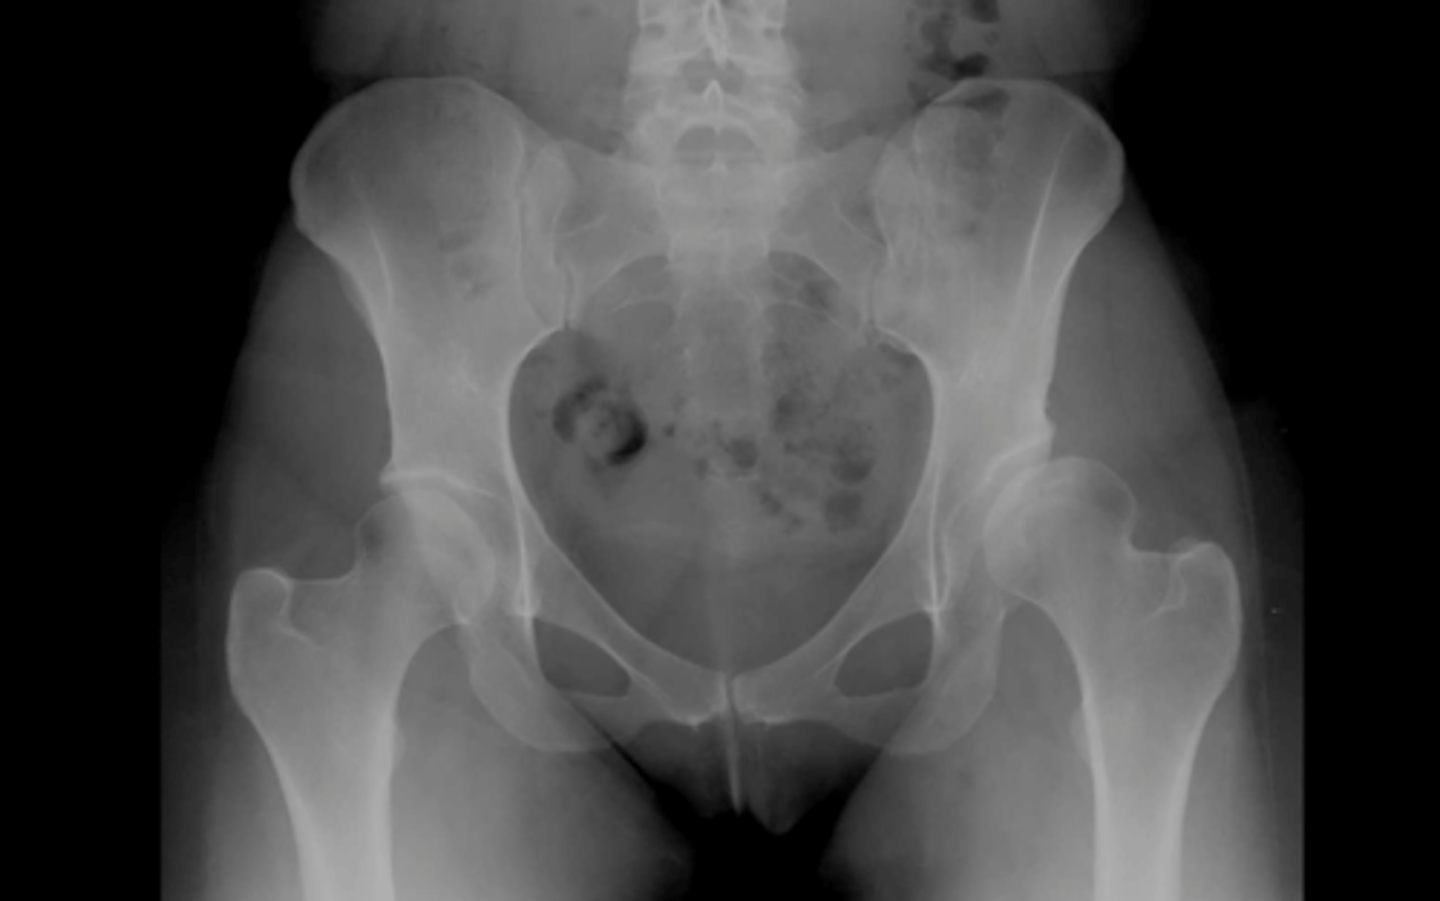

coxa valga

development of femur with angle of inclination GREATER than expected

*involves femoral head/neck and shaft

coxa vara

development of femur with angle of inclination LESSER than expected